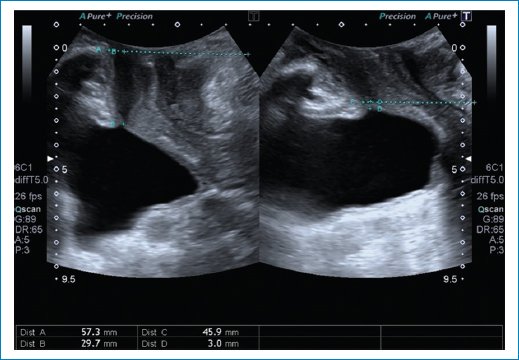

Compartimento medio5

• – Integridad de vagina (quistes vaginales [Fig. 13], leiomioma vaginal), morfología de la vagina (integridad del haz puborrectal).

• – Útero y el cuello uterino: podemos evaluar el descenso del útero vs. elongación del cuello uterino. Se evalúa el descenso del útero con respecto a la sínfisis del pubis y se toma de referencia el cuello uterino o el fondo de saco de Douglas en caso de histerectomía. Prolapso: 15 mm por debajo de la línea de la sínfisis del pubis (Fig. 14).

Figura 13. Se observa la presencia de un quiste que se extiende a lo largo de la cavidad vaginal.

Figura 14. Se observa el cuello uterino que ocupa la cavidad vaginal.